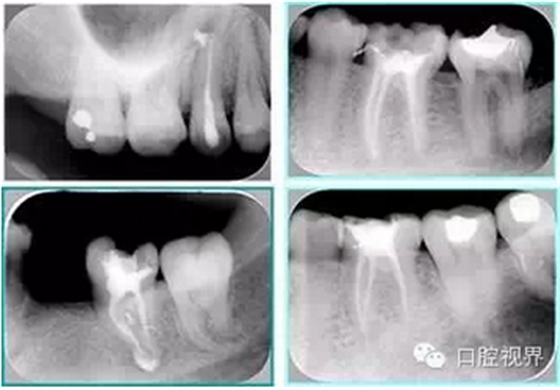

6. 術后 X 線片

術后 X 線片用來評定根管充填 長度、致密度(管壁清晰、側枝)等指標。

左圖為根管充填術后 X 線片。圖中可見,根管充填較好。右下圖有白色小點,為側方加壓導致糊劑擠出所致,表明根管充填比較致密。

致密、恰到好處的充填可去除干凈根管里感染灶,機體逐漸恢復。

多根牙時候需進行偏移投照,正位投照無法說明具體哪根牙根管充填效果。